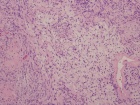

50 year old male with a several year history of right ankle mass, which the patient states has gotten larger in the past few months. On PE he has a tender, egg shaped mass in the distal posterior aspect of his left calf.

Zoom image: Cell stain Cell stain.